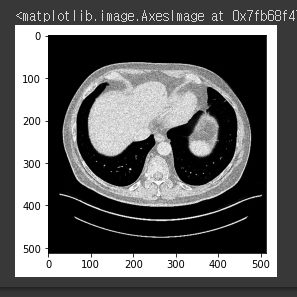

{Fig.01 raw image data}

위와 같은 이미지들에서 Liver reigon을 Segmentation 하는 것이 목적이다.